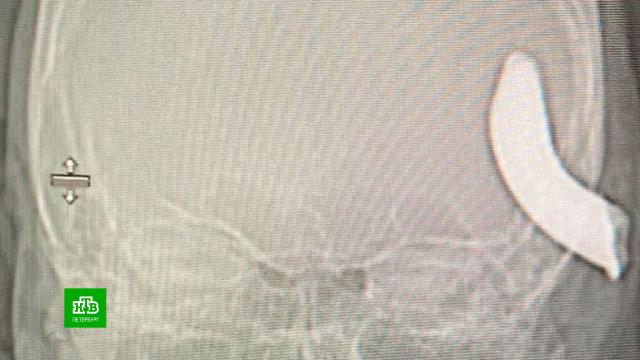

В Елизаветинскую больницу мужчину доставили в тяжелом состоянии с нарушениями речи и движения конечностей. Компьютерная томография показала, что внушительная часть металлического предмета застряла в височной доле. Также на снимках были видны и частицы крюка в головном мозге.